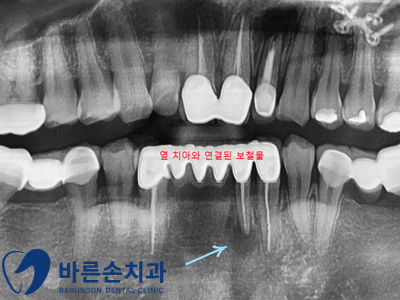

왼쪽 아래 잇몸에 통증이 심해 불편하다며 내원해 주신 환자인데요.

먼저 파노라마 촬영을 진행하고 확인해 봤습니다.

파란색 화살표를 보시면 치아 끝 어두운 원형이 보이시나요??

오래 전 신경치료를 마친 치아 뿌리에 염증이 생겨 있네요

여러 치아를 연결하여 사용하는 브릿지 보철물의 지대치 중 하나입니다.

나머지 치아들은 정상적인 상태이고, 브릿지 보철물을 뜯기엔 너무 큰 공사(?)이기 떄문에

해당 치아만 <치근단절제술> 을 하여 살려보기로 하였습니다!!